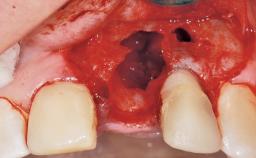

A 30-year-old female patient was referred to the office for the treatment of tooth 11. Her chief concern at the initial visit was to inquire, “Why is my tooth pink?” Upon clinical examination, it was determined that tooth 11 had a previous history of trauma and that the clinical crown had become noticeably pink in color as a result of internal resorption. This diagnosis was confirmed radiographically, indicating a large radiolucency involving the central and distal portions of the clinical crown. It was determined that restoration of this tooth was not possible, and that extraction was indicated. The presence of a mid-line diastema, which the patient wanted to reproduce, directed the treatment plan for tooth replacement utilizing a dental implant.

Placement Protocol Immediate implant placement

Tooth Site Maxillary incisor or canine

Socket Morphology Single-root socket

Socket Integrity Sufficient, with intact bone walls

Bone Volume Sufficient, with intact walls

Bone Augmentation Horizontal|Simultaneous

Augmentation Materials Autogenous chips|Membrane